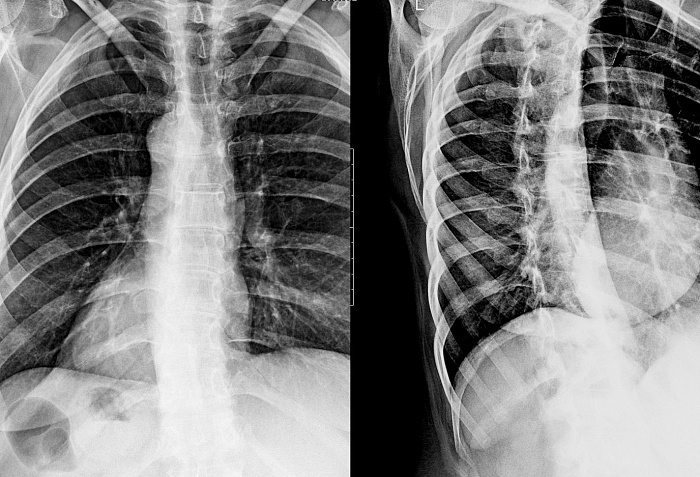

Рентгенография одного отдела позвоночника в косых проекциях – дополнительный вид исследования, который позволяет оценить состояние отдела позвоночника.

Диагностическая услуга выполняется в одной или двух проекциях.

Исследование позволяет получить дополнительную информацию по анатомической локализации патологических изменений.